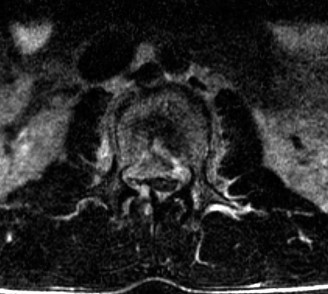

The options for definitive treatment of cervical facet dislocations? CASE 24 A 23-year-old man presents to your emergency room with severe back pain after a 30-foot fall out of a tree while intoxicated 3 hours earlier. He reports no neck pain, no upper extremity weakness or numbness, though he states that he feels weak in his legs and numbness in his groin. Currently, he is awake, alert, oriented, and cooperative and does not appear to be intoxicated. Vital signs included a blood pressure of 100/60 and heart rate of 95 beats per minute. Physical examination demonstrates midline tenderness of the lumbar spine with no palpable gap or step-off. Upper extremities show full strength and sensation. Lower extremities examination shows 2/5 bilateral strength in hip flexion and knee extension, 3/5 bilateral strength of ankle dorsiflexion, big toe extension, and ankle plantar flexion. Rectal tone is normal. Sensation to light touch and pin prick is diffusively decreased in both lower extremities and in the perineum. Bulbocavernosus reflex is present. A CT scan of his cervical and thoracic spine is negative. CT images of his lumbar spine are shown in Figures 1–32 and 1–33.

Figure 1–32

Figure 1–33

The injury of L2 is best described as which of the following?

Discussion

The correct answer is (B). The CT images reveal a comminuted fracture of the L2 vertebral body with involvement of its posterior aspect. The distinguishing feature between a burst fracture and a compression fracture is involvement of the posterior aspect of the vertebral body. Furthermore, burst fractures demonstrate that the posterior body fragments are no longer in continuity with the posterior elements (i.e., pedicles). Thus, they are free fragments that often are retropulsed into the spinal canal. Lamina fractures are often concomitant at the level of a burst fracture. By themselves, they do not infer injury to the posterior ligamentous complex. They can, however, be associated with dural tears and nerve root entrapment. Flexion–distraction injuries, also known as Chance or seat belt injuries, demonstrate widening of the posterior elements, either between the spinous processes, gapping at the facet joints, or through fractures in the posterior elements. There can be varying degrees of vertebral body compression, though typically not with comminution of the posterior vertebral margin. Fracture-dislocations can present with various

fractures of the anterior or posterior elements. The hallmark feature is a translation deformity that can be noted by misalignment of the vertebral bodies in the coronal and/or sagittal planes. A lumbar spine MRI is obtained, images from which are shown inFigures 1–34 and 1–35. Based on the information presented, the type of neurological injury is best characterized as which of the following? 1. Cauda equina injury

Figure 1–34

Figure 1–35

The correct answer is (A). The MRI demonstrates the L2 fracture with canal compromise. In this patient, the conus medullaris of the spinal cord terminates at the T12–L1 level. The fracture is at the L2 level. Thus, the neurological injury is at the level of the cauda equina, distal to the conus medullaris and spinal cord. The patient’s neurological examination is consistent with this type of injury with the presence of lower extremity weakness, intact rectal tone, and perineal numbness, though this can vary.